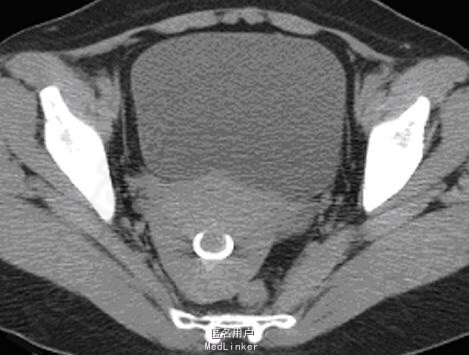

女性,42岁,上环15年。

【影像表现】 后位子宫,大小形态正常,包膜光整,实质回声均匀,宫内见节育环回声,位置正常。CT扫描示子宫大小及形态未见明显异常,肌层密度均匀,宫腔内可见一节育环密度影,位置未见异常。

【诊断】 宫腔内节育环 【鉴别诊断】 宫腔内异物

【讨论】子宫内放置节育器是最简单有效的避孕方法,节育器有多种形状,国内以金属圆形单环最多见,其次为“T”形及花瓣状。 1.影像诊断要点:① 盆腔X线透视及平片可对其位置和形状做出准确的诊断;② 超声检查可见宫腔内强回声节育环回声;③ CT检查可见宫腔内的金属密度节育环影,以上几种检查都可对节育环的位置及形状做出准确的诊断。 2.鉴别诊断:主要与宫腔内异物及钙化鉴别,后者多为形态不规则或有特定形态,结合临床病史即可做出鉴别诊断。